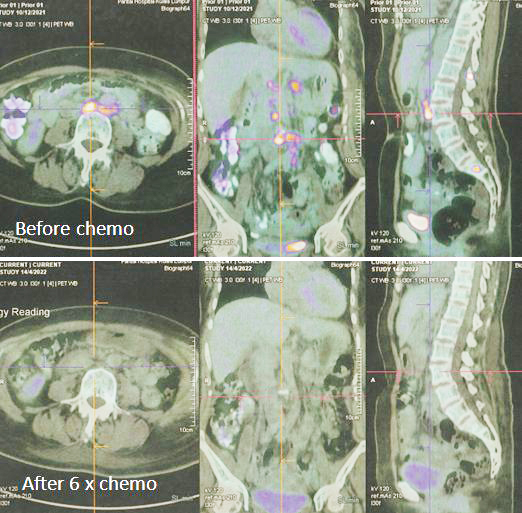

8. PET scan on 14 April 2022 showed good response indeed.

1. Amazing results of chemotherapy. Compare these three pictures –

Left: After surgery Lucy was on alternative therapy, refusing to undergo chemotherapy. The result was extensive metatastasis (middle). Right: Lucy has no choice but to go for chemotherapy. The outcome of 6 cycles of chemotherapy was just fantastic! In my 25 + years dealing with cancer patients, I have never seen such a great outcome of chemotherapy. Salute the oncologist! You rescued her!

In fact, the results were so unbelievable that one is tempted to ask if it is for real and not a fake? My answer is NO, detailed study of the PET scan results below are real! Study the images carefully – those before and after  chemotherapy.

The one lesson I learnt is that while chemotherapy had earned bad reputation there are times that chemo did help and can save your life. So let us be open minded. There is no one rule for treating cancer.

2. Is Lucy cured of her cancer? Even though PET scan showed complete response to the treatment, does it mean Lucy is cured? Unfortunately, the answer is NO. The cancer may come back after a period of time.